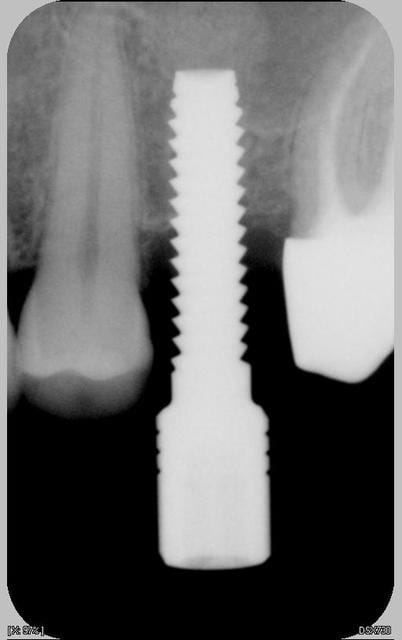

Les images de son cas sont superbes, mais la technique décrite par Growler n'est-elle pas dangereuse?

- pourquoi forage à... 8mm?????: selon Palti et... ,il faut arrêter son forage à 2mm environ de la corticale du plancher (d'où l'interet de connaitre avec exactitude la hauteur d'os sous -sinus: scan), pour être sur de ne pas perforer la corticale, la membrane....peut-on se fier à son seul sens "tactile"...?.

-pourquoi utiliser un autre foret que le 2mm, quand on trouve sous les sinus, dans 90% des cas, de l'os type I (selon mon humble expérience)et que l'on sait que toute la stab. primaire de l'implant repose sur son "accroche "dans les "quelques mm" d'un tel os et d'1 ou 2 corticales type "papier à cigarette" ,...??? pouquoi ne pas "élargir " le "tunnel créé au foret 2mm" avec des "expanseurs"(par exemple: dans la boite "à Summers" de hu-friedy, il ya des spreaders permettant depasser de 2 à 2,7, puis 2,7à 3,2, puis 3,2 à3,7, 3,7 à4,2...) : çà permet même de respecter un sous-forage de 7-8/10°mm pour un Tekka de 4 ou 4,5 ou 5...

- le fait de "pousser" le matériau "directement de 8 à 13mm, soit sur 5mm, ne présente-il pas non plus un risque pour la membrane...?

dans ce cas j'avais intérêt à utiliser d'autres forets que le 2 mm car l'os était plus dense qu'on pouvait le penser, à tel point que j'ai même utilisé le foret terminal (ce dont je me passe habituellement dans le cas de faible densité). J'ai dû terminer la mise en place de l'implant à la clé à cliquet.